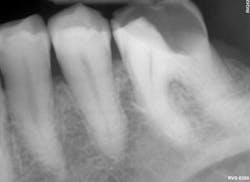

Furthermore, Activa BioActive Bulk Flow provides an option for dentists who appreciate Activa’s bioactive properties but want to work without a dispenser. Activa BioActive Bulk Flow simplifies inventory thanks to ShadeFusion universal color matching. The material is sufficiently radiopaque so dentists can be confident that it will be visible for any clinician evaluating their patient for years to come.